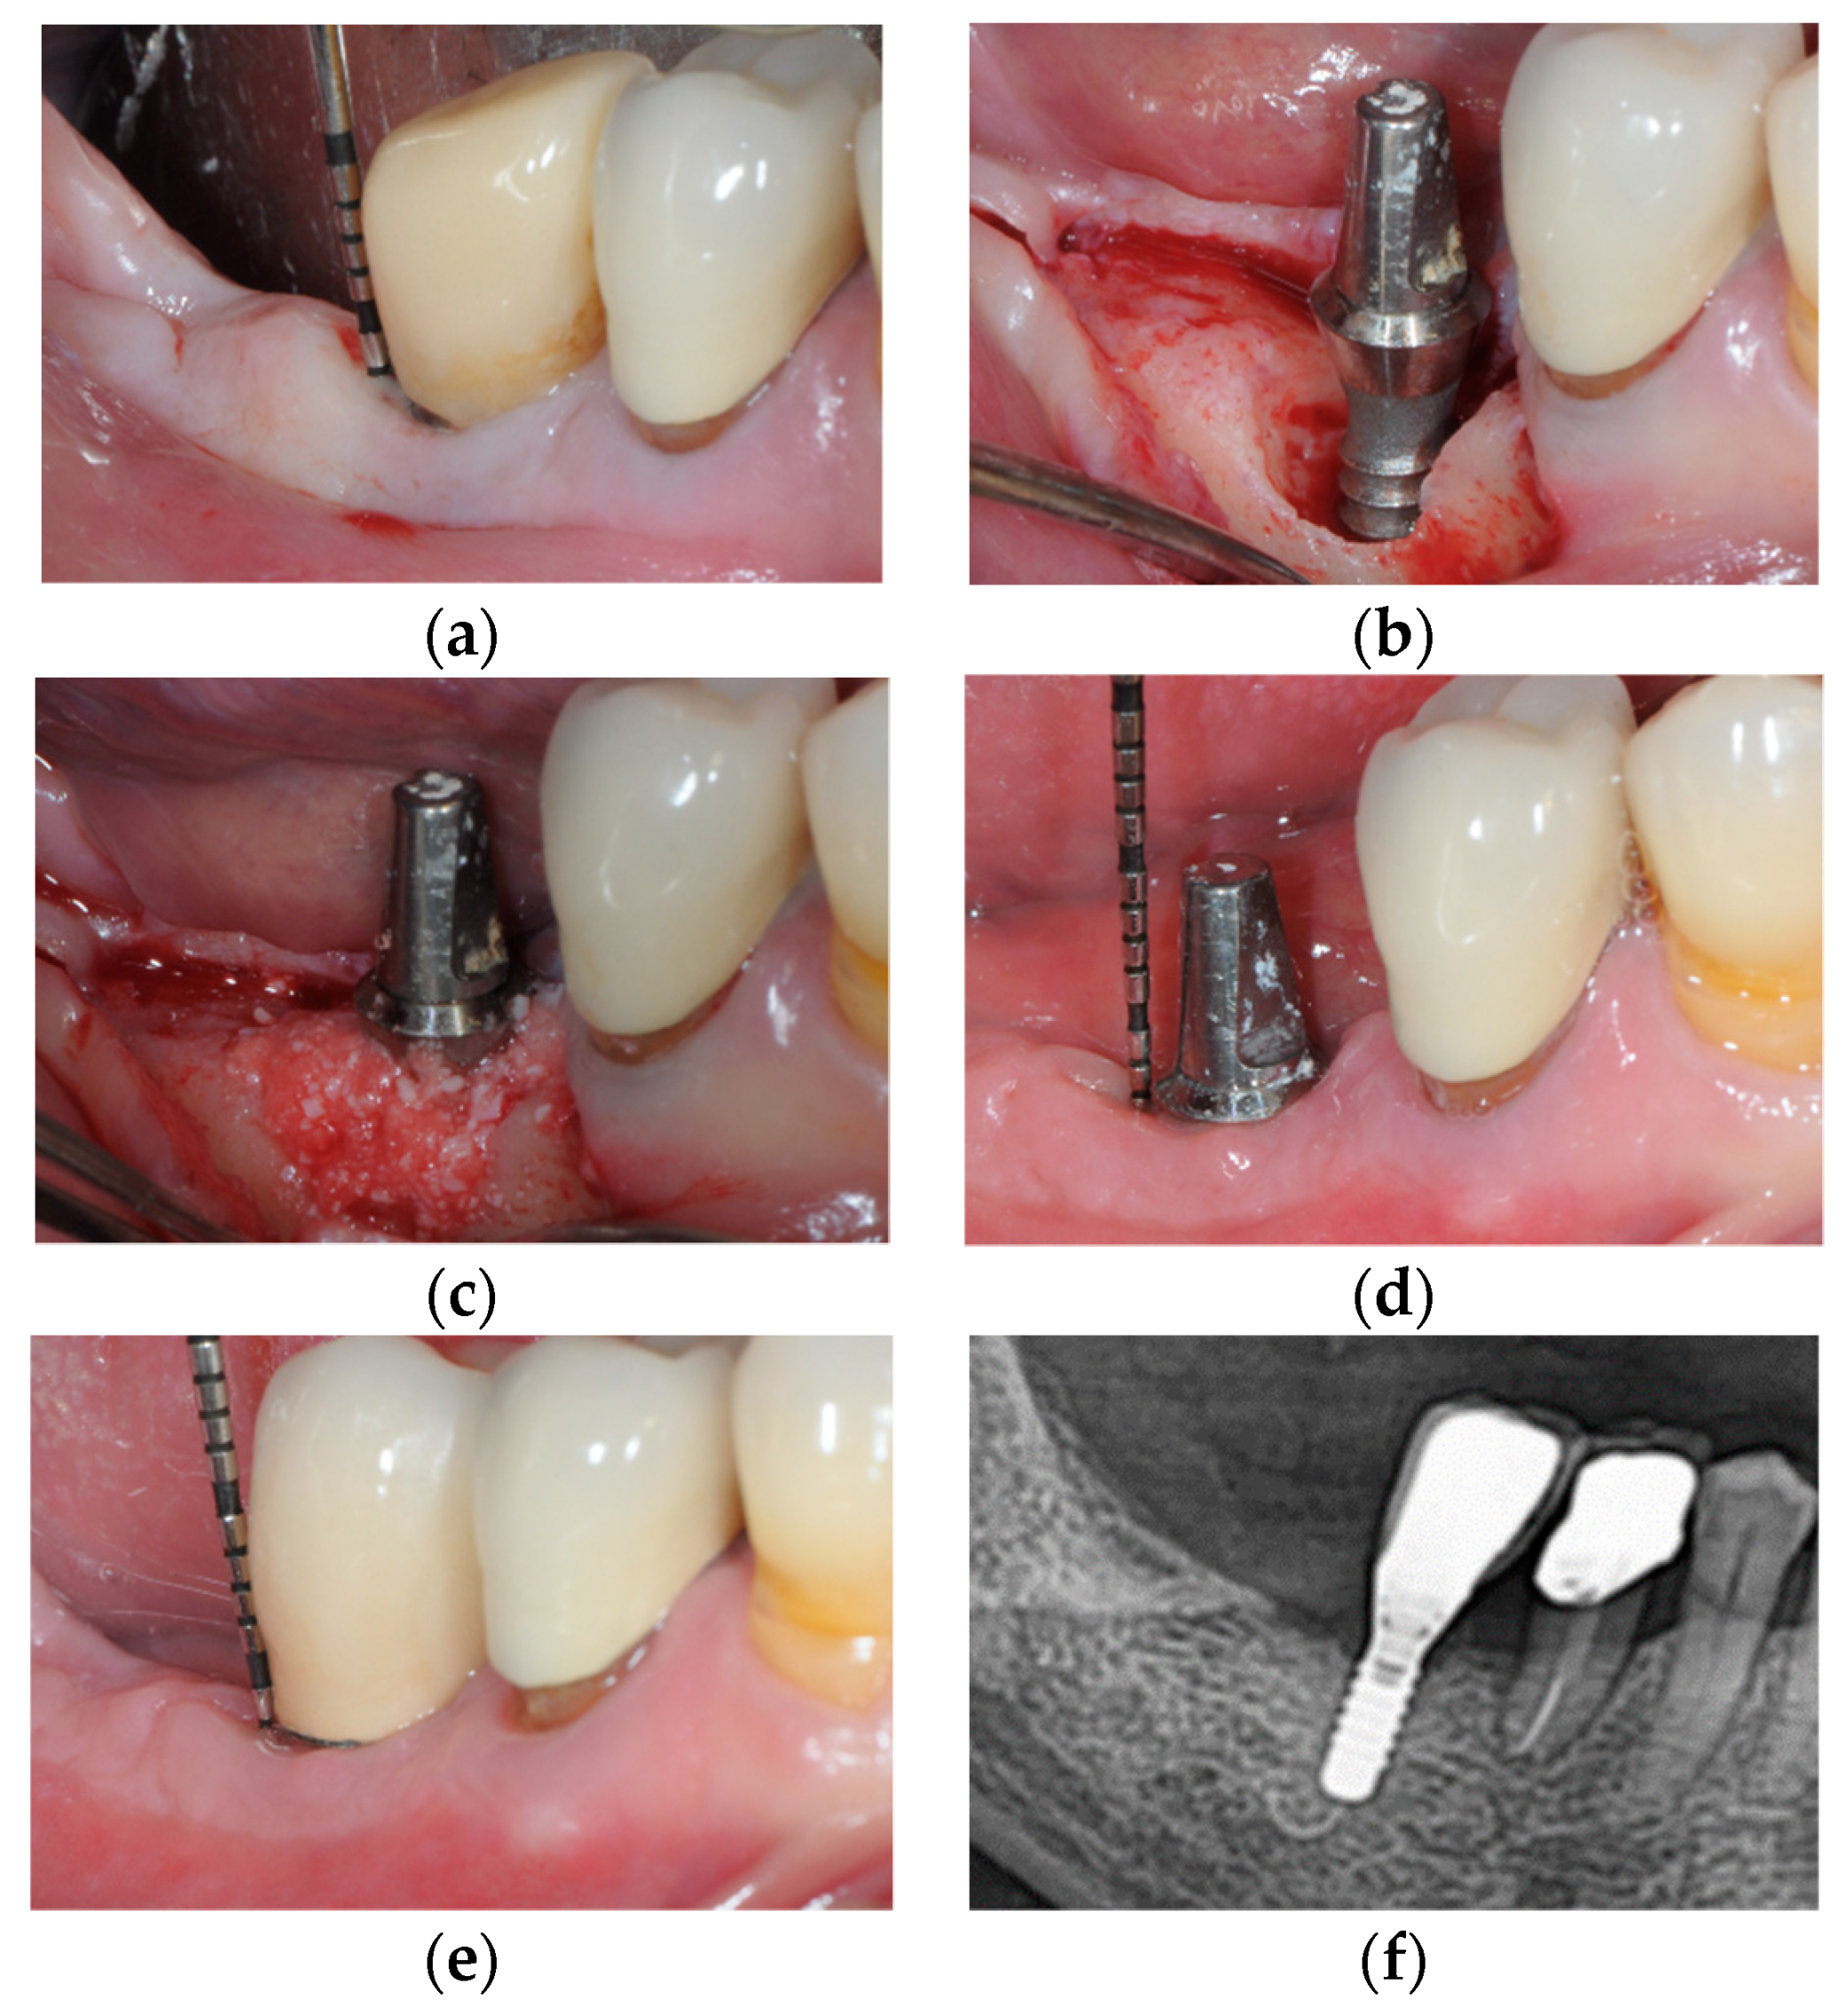

- Monje, A.; Pons, R.; Roccuzzo, A.; Salvi, G.E.; Nart, J. Reconstructive therapy for the management of peri-implantitis via submerged guided bone regeneration: A prospective case series. Clincal Implant Dent. Relat. Res. 2020, 22, 342–350. [Google Scholar] [CrossRef] [PubMed]